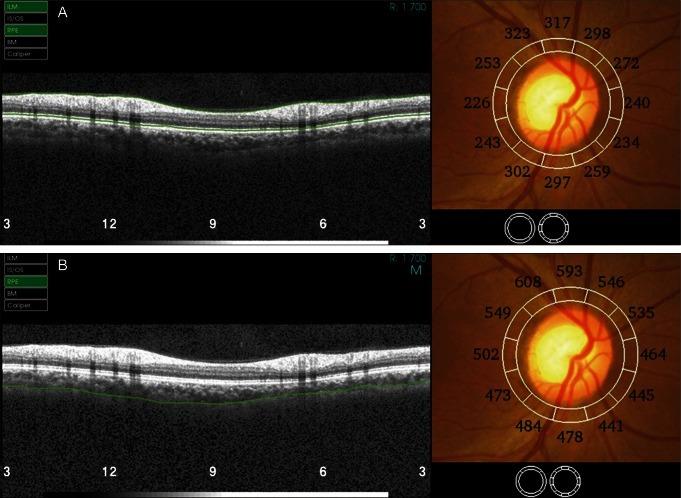

To evaluate a simplified method to measure peripapillary choroidal thickness using commercially available, three-dimensional optical coherence tomography (3D-OCT).

3D-OCT images of normal eyes were consecutively obtained from the 3D-OCT database of Korea University Medical Center On the peripapillary images for retinal nerve fiber layer (RNFL) analysis, choroidal thickness was measured by adjusting the segmentation line for the retinal pigment epithelium to the chorioscleral junction using the modification tool built into the 3D-OCT image viewer program. Variations of choroidal thickness at 12 sectors of the peripapillary area were evaluated.

We were able to measure the peripapillary choroidal thickness in 40 eyes of our 40 participants, who had a mean age of 41.2 years (range, 15 to 84 years). Choroidal thickness measurements had strong inter-observer correlation at each sector (r = 0.901 to 0.991, p < 0.001). The mean choroidal thickness was 191 ± 62 µm. Choroidal thickness was greatest at the temporal quadrant (mean ± SD, 210 ± 78 µm), followed by the superior (202 ± 66 µm), nasal (187 ± 64 µm), and inferior quadrants (152 ± 59 µm).

The measurement of choroidal thickness on peripapillary circle scan images for RNFL analysis using the 3D-OCT viewing program was highly reliable and efficient.

评估一种使用商用三维光学相干断层扫描(3D-OCT)测量视乳头周围脉络膜厚度的简化方法。

从韩国大学医学中心的3D-OCT数据库中连续获取正常眼睛的3D-OCT图像。在用于视网膜神经纤维层(RNFL)分析的视乳头周围图像上,使用3D-OCT图像查看程序中内置的修改工具,将视网膜色素上皮的分割线调整到脉络膜巩膜交界处来测量脉络膜厚度。评估视乳头周围区域12个扇区的脉络膜厚度变化。

我们能够在40名参与者的40只眼中测量视乳头周围脉络膜厚度,这些参与者的平均年龄为41.2岁(范围为15至84岁)。各扇区的脉络膜厚度测量在观察者间具有很强的相关性(r = 0.901至0.991,p < 0.001)。平均脉络膜厚度为191±62μm。脉络膜厚度在颞侧象限最大(平均值±标准差,210±78μm),其次是上方(202±66μm)、鼻侧(187±64μm)和下方象限(152±59μm)。

使用3D-OCT查看程序在用于RNFL分析的视乳头周围环形扫描图像上测量脉络膜厚度是高度可靠且有效的。